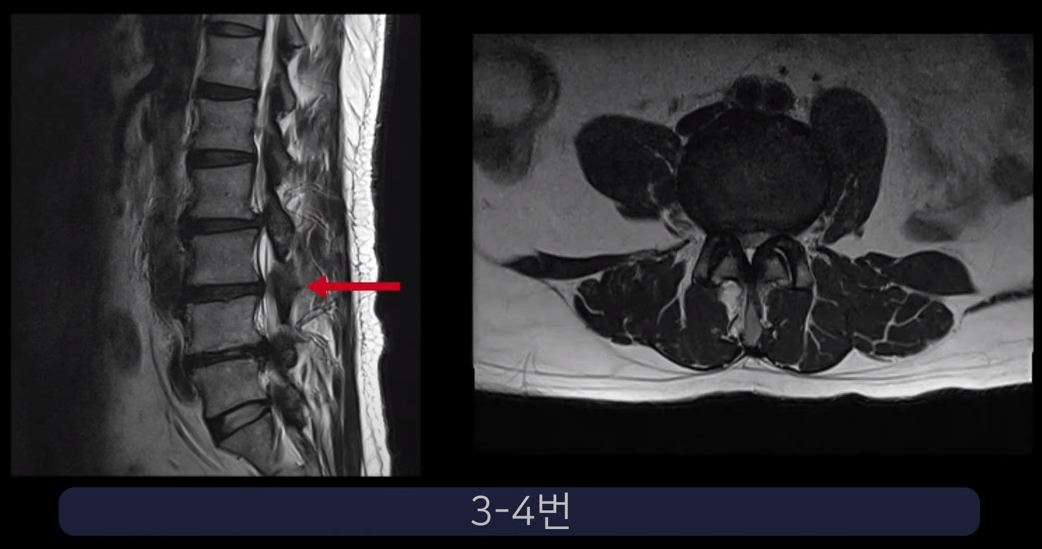

실제 척추관과 추간공이 심하게 막힌 두 환자 케이스를 보여드리겠습니다.

첫 번째 환자분입니다. 이 환자분은 허리 세 마디에 심한 협착이 있습니다. 2-3번, 3-4번, 4-5번 이렇게 척추관이 세 마디가 심하게 막혀있습니다.

25년간 허리에 신경주사를 맞아왔는데 이젠 효과가 전혀 없고, 작년부터 거의 걷지 못하는 상태가 되어 수술을 결심하였습니다. 대학병원에서 수술이 어렵다고 했고 유명 척추병원에서 3주에 걸쳐 3번의 수술을 권했습니다.